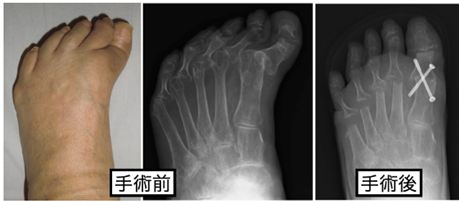

昔からある方法は切除関節形成術です。関節が重度に破壊されている場合に選択される手術です。

- ホフマン法など: 重度の変形や痛みを伴う場合に、中足趾節(MTP)関節の骨の一部を切除して痛みを和らげ、歩行機能を改善します。

骨切り術: 骨の一部を切って形を整えることで、関節を温存し、足趾のアライメントを改善します。